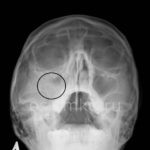

Представленный ниже рентгеновский снимок чётко демонстрирует наличие синусита.

- Гайморит

Для определения внешнего вида гайморита на рентгенограмме необходимо осознать, что воспалительные изменения и накопившаяся жидкость проявляются светлыми областями на темном фоне изображения.

При нормальном состоянии придаточные пазухи на рентгеновском снимке не содержат воздуха. На изображении здорового человека они выглядят как темные области по обе стороны от носа и имеют полуовальную форму. Для определения того, является ли область синуса нормальной или патологической, ее оттенок сравнивают с оттенком глазницы. В норме цвет синусов и глазниц совпадает на рентгеновском снимке.

Уже в университетах обучают определять гайморит на рентгеновском снимке (см. фото 5). Здоровые носовые пазухи изображены темными полуовальными образованиями. Гайморит на снимке представлен затемнением в верхних горизонтальных уровнях. По снимку можно отчетливо увидеть тень с волнистым контуром – жидкость такого типа: гнойная, слизистая, катаральная.